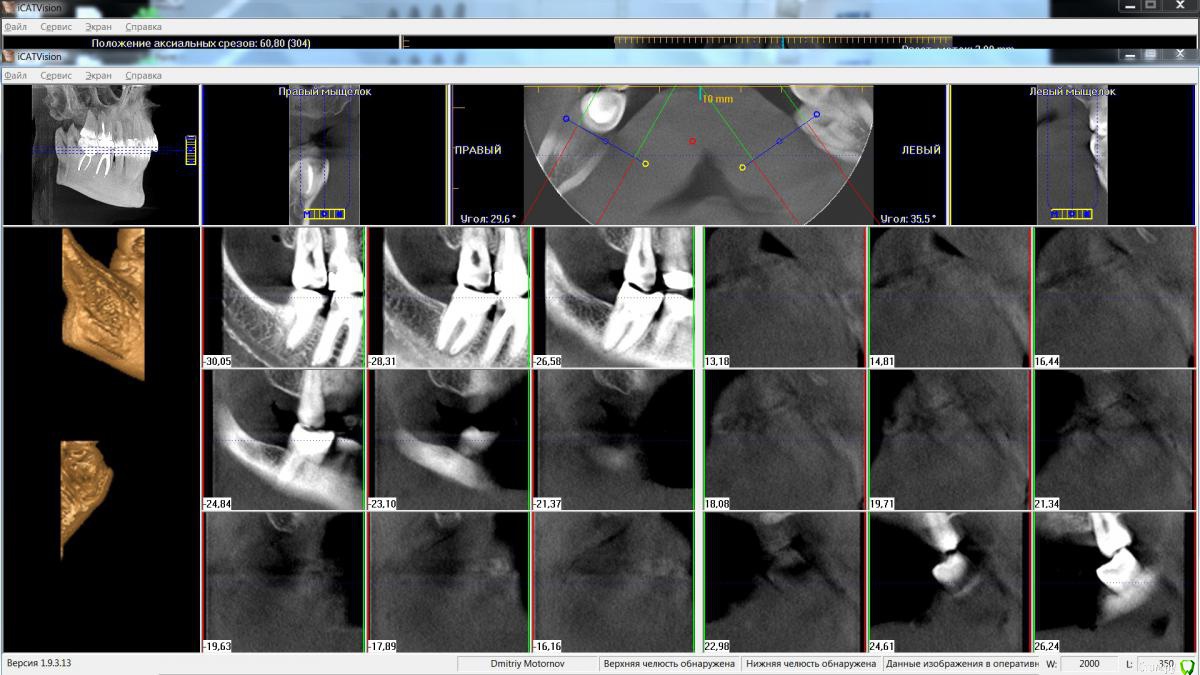

Maktub Опубликовано 13 августа, 2016 Автор Поделиться Опубликовано 13 августа, 2016 Сделал кт, дали диск с программой. Снимок оттуда выдирается или нет? Ссылка на комментарий

Maktub Опубликовано 14 августа, 2016 Автор Поделиться Опубликовано 14 августа, 2016 вот Ссылка на комментарий

Maktub Опубликовано 15 августа, 2016 Автор Поделиться Опубликовано 15 августа, 2016 По кт такие жерекомендации? Ссылка на комментарий